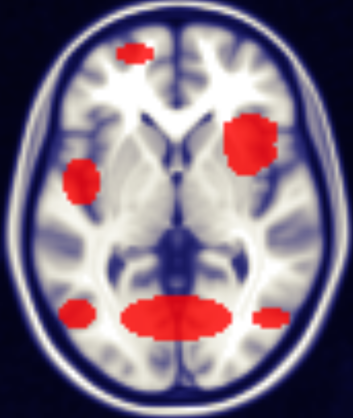

Figure 5 displays the identified regions overlaid on the brain image — Medial Area 6, Medial Area 10, Area V5 of the Visual Cortex (also known as the middle temporal area (MT)), Occipital Polar Cortex, Ventral Dysgranular and Granular Insula, and Dorsal Dysgranular Insula. These regions exhibit significant sex-related differences in regional CBF, highlighting their importance as key discriminative features in sex classification models based on perfusion data.

Medial Areas 6 and 10 are part of the Brodmann’s areas (BA), a classical cytoarchitectonic mapping of the cerebral cortex widely used to relate brain structure to function. Brodmann Area 6 includes the supplementary motor area (SMA), a region critical for motor planning, coordination, and execution, especially for complex and bilateral movements. Brodmann Area 10, located in the anterior prefrontal cortex, is among the largest and most evolutionarily advanced prefrontal regions, implicated in high-level cognitive functions such as working memory, decision-making, and goal-directed behavior. These medial frontal regions are metabolically demanding and highly sensitive to changes in cerebral perfusion [49].

Our findings show pronounced age- and sex-dependent declines in CBF intensity in these Brodmann areas, with males exhibiting a greater reduction than females [50]. This pattern aligns with established evidence of sex differences in vascular aging and neurovascular coupling, influenced by hormonal factors such as estrogen, which is known to have vasoprotective and metabolic regulatory effects. The progressive CBF decline in these areas likely reflects cumulative cerebrovascular burden that contributes to impairments in motor control and executive functions seen in aging populations. Conversely, the relatively preserved perfusion observed in females may underlie their relative resilience against early neurovascular dysfunction.

Other regions, including Area V5 (MT) and the Occipital Polar Cortex—key nodes in visual motion processing and early visual perception—also show higher perfusion in females, potentially linking to sex differences in visual attention and sensory processing. The Ventral and Dorsal Dysgranular Insula, integral to the salience network and involved in interoceptive awareness, emotion regulation, and cognitive flexibility, exhibit female-biased perfusion increases, supporting sex-specific patterns of affective and adaptive neural processing.

Together, these neurovascular differences emphasize distinct sex- and age-related vulnerabilities and adaptations across motor, cognitive, sensory, and emotional brain networks. The medial Brodmann areas 6 and 10, in particular, emerge as critical biomarkers of cerebrovascular aging and sex-specific neural health, reinforcing their significance in data-driven models for sex classification based on CBF metrics.